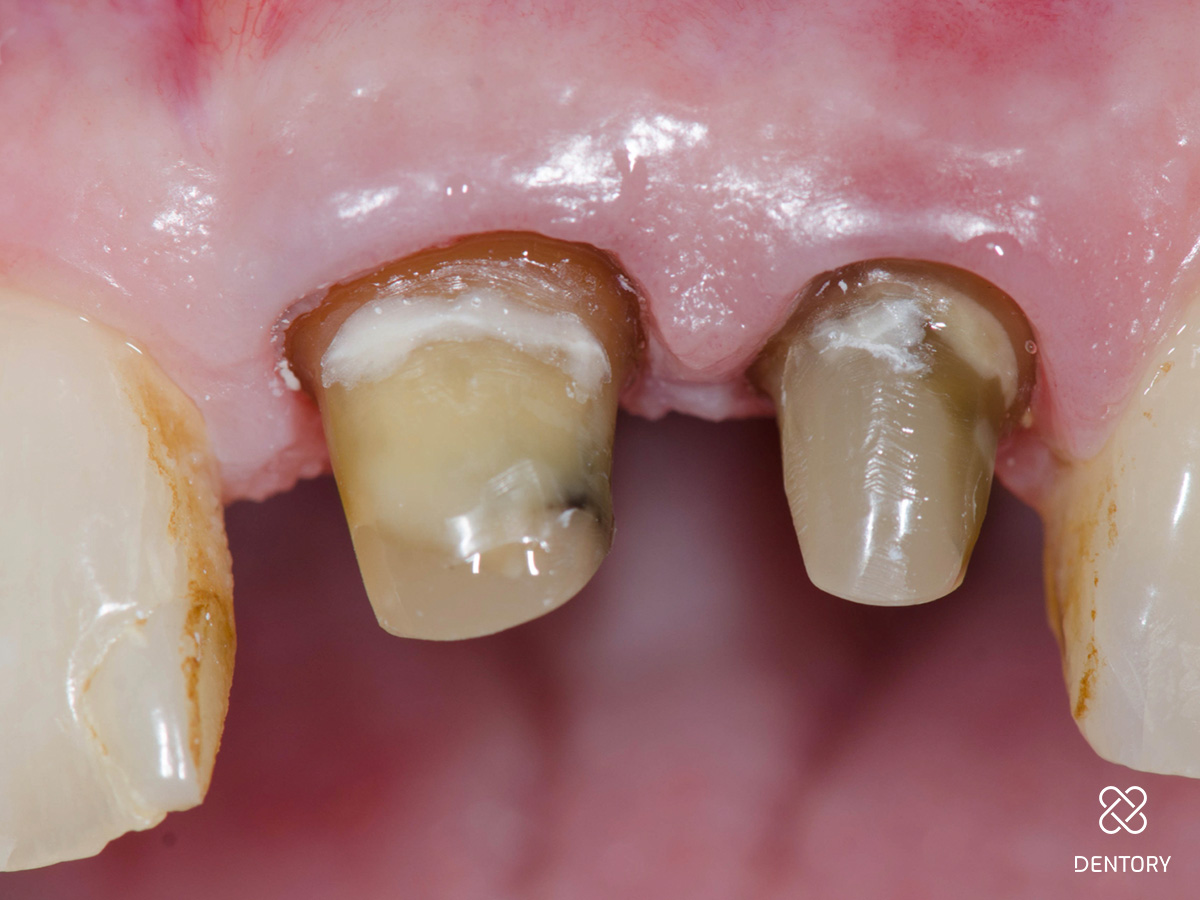

Abbildung 1

Ausgangssituation: Bei einer Routineuntersuchung einer 70-jährigen Patientin...

Abbildung 2

wurden ein ästhetisches Defizit wegen insuffizienter Kronenränder sowie Sekundärkaries an den Zähnen 21 und 22 diagnostiziert.